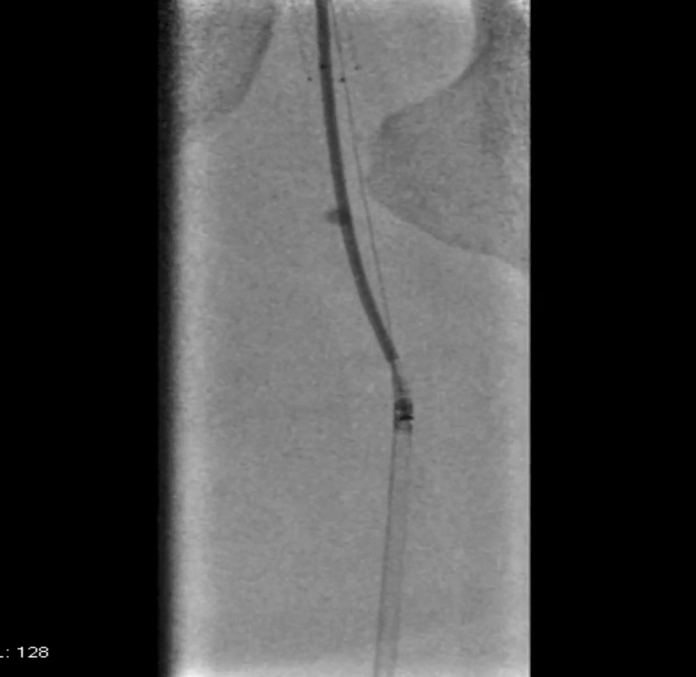

先用5mm长球囊充分预扩张;再次造影显示,股浅动脉近中段管腔获得良好,中远段仍有大量的夹层

采用药物涂层球囊(DCB)对股浅动脉病变段全程覆盖:近端用5-250新型药涂球囊,远端用5-150 impact 药涂球囊;

造影显示中段仍有局限性夹层,为保证远期通畅率,植入补救性支架并以5mm球囊后扩张